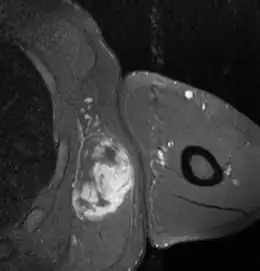

RMN con contraste de liposarcoma mixoide de alto grado en región axilar izquierda en hombre de 40 años.